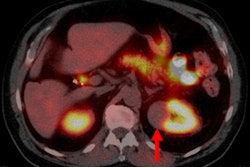

An indeterminate renal mass is a lesion that can't be confidently diagnosed as benign or malignant when it's found, Raimondi said. These lesions can have enhancement on CT between 20 HU and 70 HU, have intermediate signal intensity on MRI, and be isoechoic or hypoechoic on ultrasound.

Contrast-enhancement wash-in is a typical sign for a malignant solid renal mass, but some benign lesions can also show contrast wash-in, such as oncocytomas. In addition, 17% to 20% of renal tumors are hypovascular on cross-sectional imaging. Furthermore, contrast enhancement of 10 HU to 30 HU -- a level considered to be pseudoenhancement -- can't be confidently suggestive of malignancy, Raimondi said.

To address this problem, the researchers set out to explore the role and diagnostic value of CEUS for these masses. The study, which was performed from January 2012 to July 2015, included 39 patients (25 men, 14 women; age range, 40-81) who had hypovascular small renal masses with an inconclusive contrast enhancement pattern on CT or MRI. Of these, 32 patients had masses identified on contrast-enhanced CT and seven had masses found on contrast-enhanced MRI.